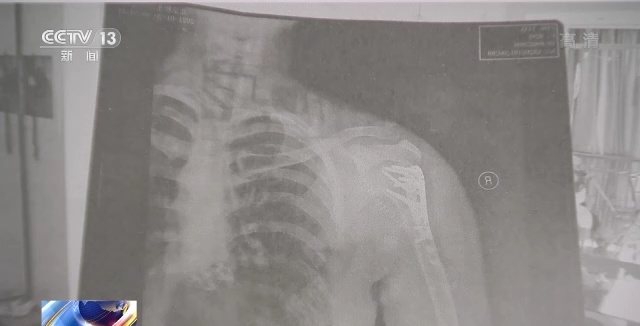

经过医生诊断,庞女士右侧肱骨骨折。当天,这家密室的经营者垫付了庞女士的医疗费。而这之后,双方在后续赔偿上一直未能达成一致,庞女士认为,正是由于密室场所存在安全隐患,商家在经营过程中没有尽到人身安全保障义务,才致使自己受伤的。